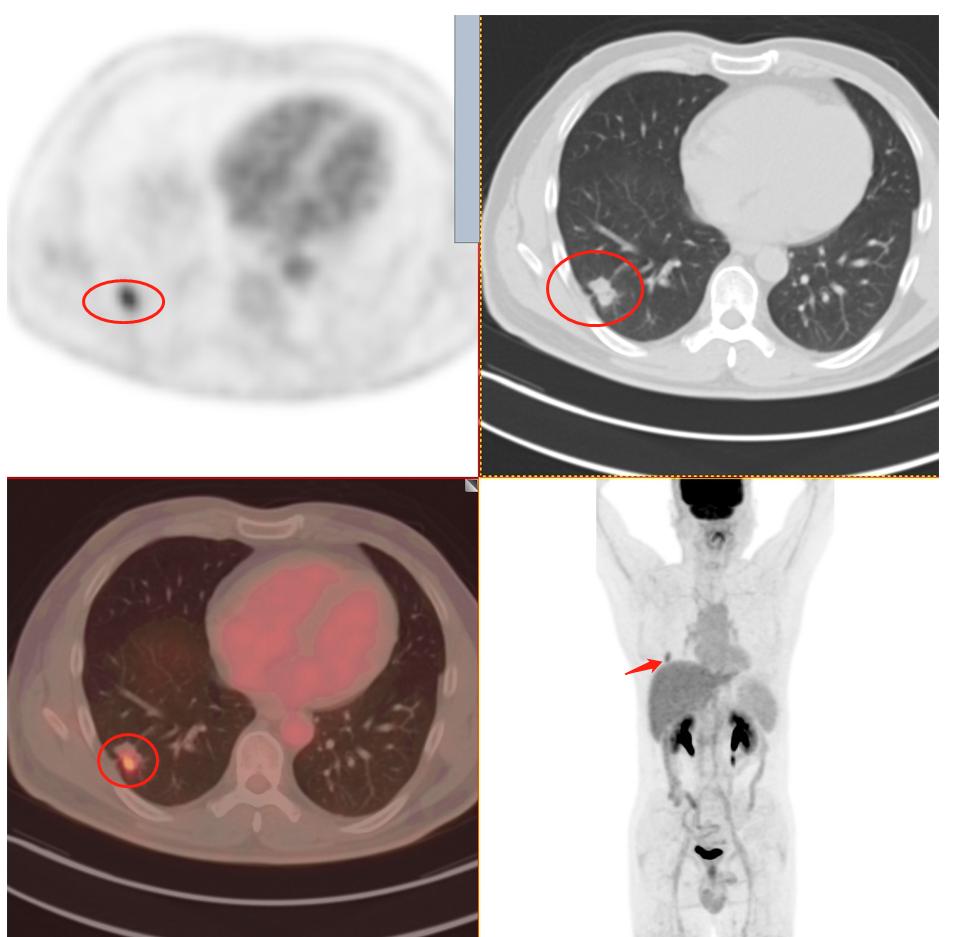

下面我们看PET/CT检查后的情况:

患者1:图3

毫无疑问PET/CT检查18-F-FDG葡萄糖代谢增高,再一次增强了肺癌的诊断信心,影像学可以肯定的诊断为周围型肺癌。其余所示结节未见FDG代谢增高,考虑为慢性炎性结节及钙化灶。

患者1:图4

全身PET/CT检查其他部位未见明显异常放射性浓聚灶,即全身其他部位未发现肿瘤性病变(未见明确转移)。不幸中的万幸,患者没有转移。通过检查可以进行一个肿瘤分期:T1cN0M0 属于ⅠA3期。这一类也算早期肺癌,术后治愈率不错。